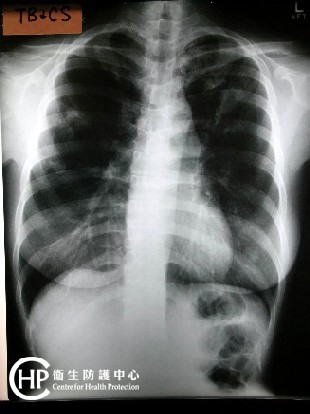

衞生防護中心 相片集 相片集 結核病

X線診斷要點 關於 肺不張 需要弄清楚以下幾點 每日頭條